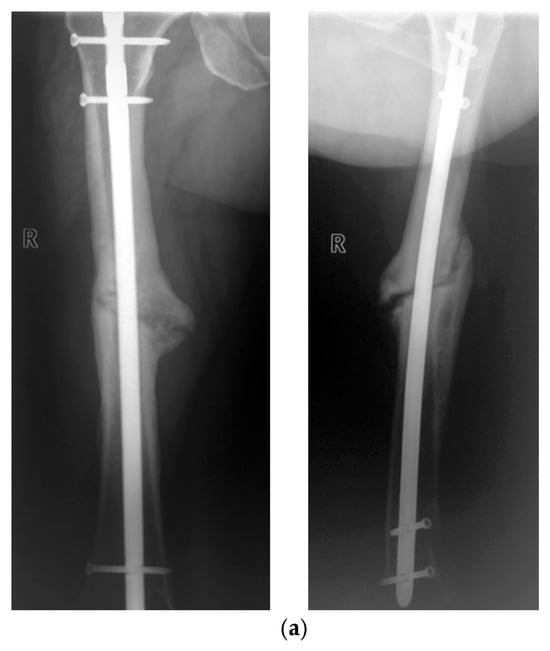

Long-Term Evaluation of Bone Healing Monitoring Using an Instrumented Plate with Measurement Sensors (Smart Implant) over 10 Years

by Arndt P. Schulz, Birgitt Kowald, Matthias Münch, Klaus Seide, Nils Weinrich, Tobias Barth and Benjamin Kienast

Sensors 2025, 25(18), 5779; https://doi.org/10.3390/s25185779 - 16 Sep 2025

A total of 66 smart implants were included. As a measure of bony stability, the relative elastic compliance of the osteosynthesis was determined from the gradient between the applied external load and the measured implant load over the entire healing process. The healing [...] Read more.

A total of 66 smart implants were included. As a measure of bony stability, the relative elastic compliance of the osteosynthesis was determined from the gradient between the applied external load and the measured implant load over the entire healing process. The healing process of non-unions of the femur with a smart implant was tracked by telemetric measurements over a timespan of up to 10 years. The measurements of the longest healing process show a very slow but constant decrease in force transmission over the implant, radiological findings over 10 years show corresponding consolidation until bony healing. The use of a telemetrically instrumented bone plate, a so-called smart implant, to monitor the healing process is a successful procedure to support the clinician in his decision to take further surgical measures or to wait until healing occurs. Full article